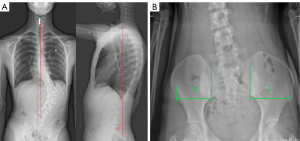

This retrospective, single-center, cross-sectional study was conducted in accordance with the Declaration of Helsinki (as revised in 2013) and was approved by the Ethics Committee of the Third Hospital of Hebei Medical University. The legal guardians of the AIS patients provided written informed consent to participate in this study. A total of 223 AIS patients with a right thoracic curve or left thoracolumbar/lumbar curve who underwent anteroposterior and lateral radiographs of the entire spine at the third Hospital of Hebei Medical University between November 2020 and December 2021 were enrolled (Figure 1). The inclusion criteria were as follows: (I) patients with AIS who underwent anteroposterior and lateral radiographs of the entire spine; (II) Cobb angle >10°; (III) aged 10–18 years; (IV) no surgical or bracing treatment; and (V) the direction of scoliosis on the right side in the thoracic segment (right thoracic curvature) and left side in the thoracolumbar/lumbar segment (left thoracolumbar or lumbar curvature), which accounted for the majority of scoliosis cases (13). The exclusion criteria were as follows: (I) patients with congenital scoliosis, including hemivertebra, butterfly vertebra, and poor vertebral segmentation; (II) scoliosis with definite etiology, including secondary neurofibromatosis, Marfan syndrome, and syringomyelia; (III) history of pelvic, hip, and lower limb diseases or abnormal function and structure; (IV) spinal tumors, history of trauma and infection, metabolic bone diseases, and congenital diseases; and (V) unclear images which may affect the measurement of relevant parameters. Patients with a left thoracic curvature and right lumbar curvature were also excluded for the following reasons. In patients with the left thoracic curvature, most of the lateral curvature was smaller, within 20°, and the main curvature was closer to the cervical spine. In patients with right lumbar scoliosis, most cases had wedge-shaped vertebral bodies in the lumbar spine, and according to the degree of vertebral body deformation in these patients, it occurred either before or after birth and belonged to the category of infantile or congenital scoliosis.

Full spine anteroposterior and lateral X-ray radiographs were obtained by a Siemens Ysio max Digital Medical X-ray photography system (Siemens, Erlangen, Germany) using a special filter grid for full-length spinal photography and a film distance of 300 mm.

Anteroposterior position: anatomical position, eyes straight ahead, hands naturally drooping, palms facing forward, both hips and knees naturally extended, and feet placed together.

Lateral position: standing naturally with hands on the support in front.

Photographs were taken by 2 technicians with over 5 years of relevant working experience. All indexes were measured by 2 clinicians with 3 years of relevant working experience and were performed on the picture archiving and communication systems (PACS; Donghua iMedical PACS 2020; Beijing, China), including the Cobb angle, clavicular angle (CA) (6), glenoid obliquity angle, acromioclavicular joint deviation or offset (14), femoral neck-shaft projection angle, iliac obliquity angle (IO) (15), acetabular obliquity angle, coronal width ratio of the left and right pelvis (L/R) (16), coronal trunk deviation distance, and spinal deformity deviation distance on the sagittal plane (17,18) (Figures 2,3). There was no missing data.